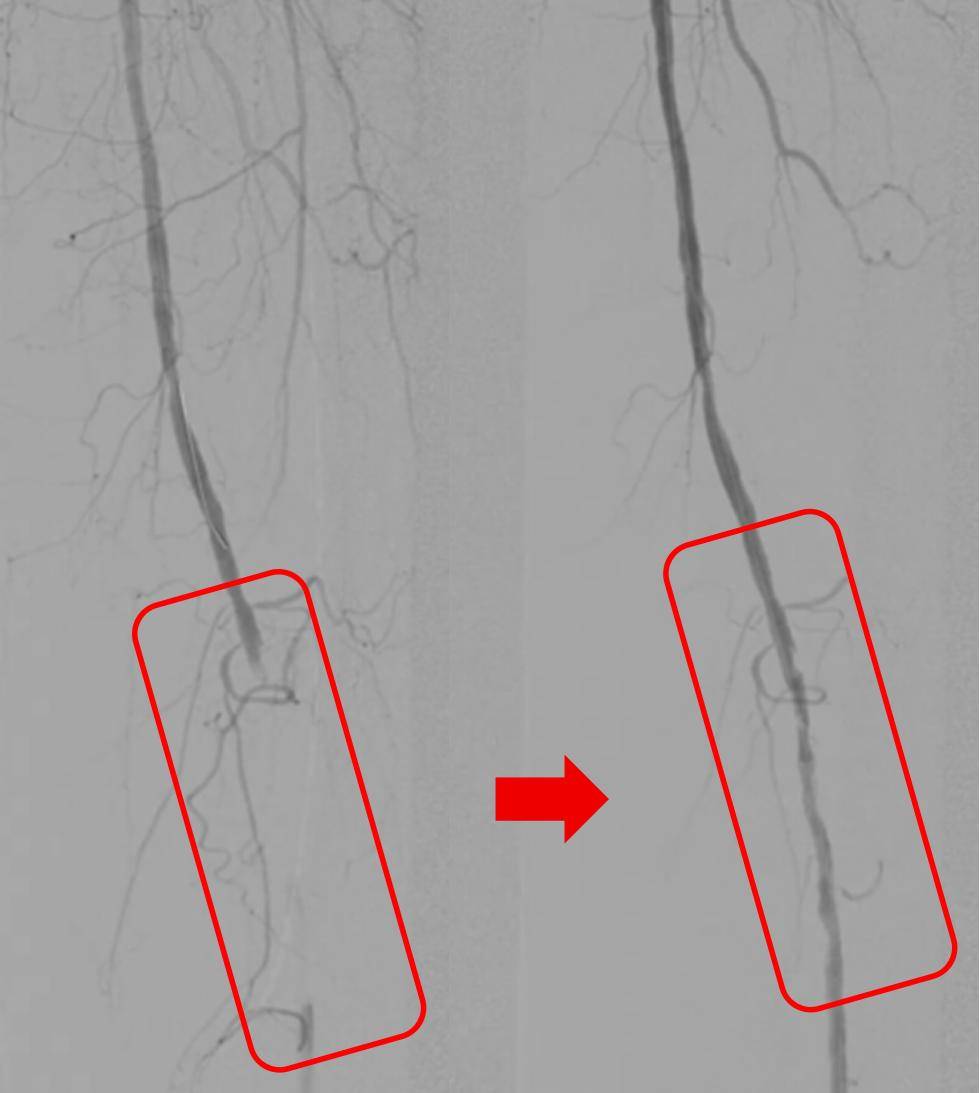

红框内的下肢动脉血栓被清除